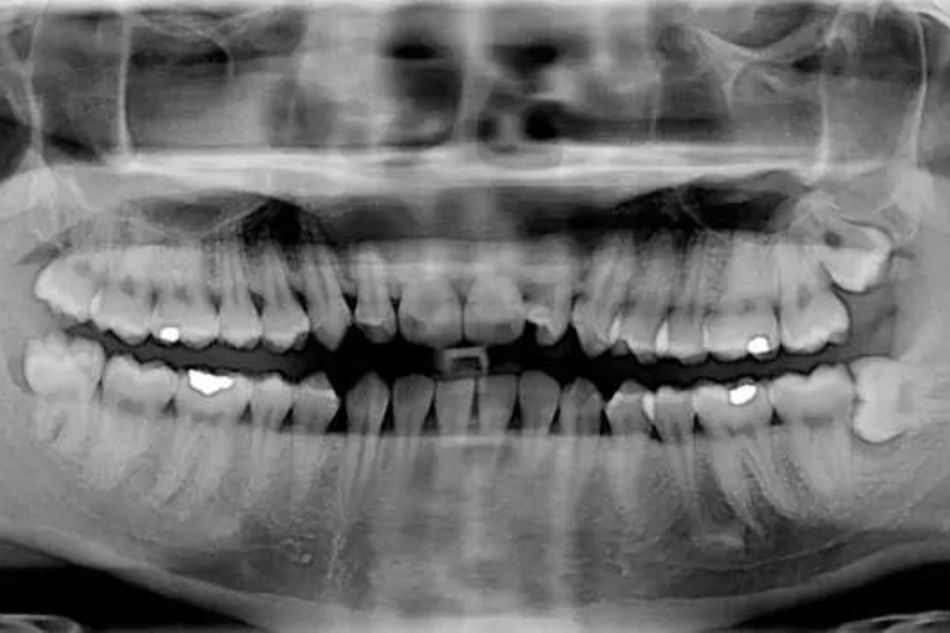

Ortopantomografia dentale e TAC dentale ConeBeam

Presso Poliambulatori San Gaetano è attiva una apparecchiatura di ultima generazione per eseguire gli esami di Tc dentale Cone-beam e OPT, Ortopantomografia.

Grazie a questa apparecchiatura possiamo eseguire esami estremamente dettagliati in 2D e 3D.

- ortopantomografia HD

- ortopantomografia CHILD